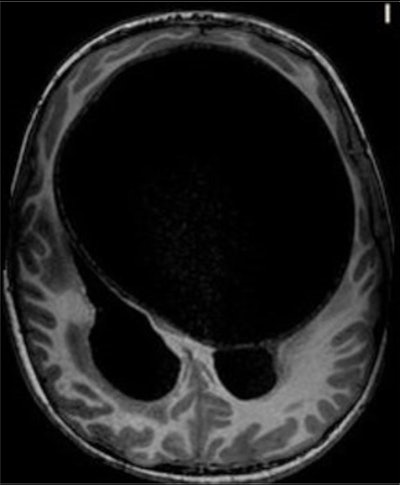

An axial T1-weighted MRI scan of a hydatid cyst. Clinical images courtesy of Carlos F. Ugas Chacape, MD.

Neurocysticercosis is still prevalent but is decreasing in Peru, whereas free-living amebiasis is less common but has a rising prevalence and is often fatal without treatment. Toxoplasmosis remains a significant congenital infection in Latin America, and it's important to be aware of hydatid disease, malaria, toxocariasis, and strongyloidiasis.

"Parasitic brain infections persist in Peru, and primarily affect underserved children with poor access to medical care," said Ugas Chacape. "Neurocysticercosis is still relevant, and the radiological features and stages in children align with adults."